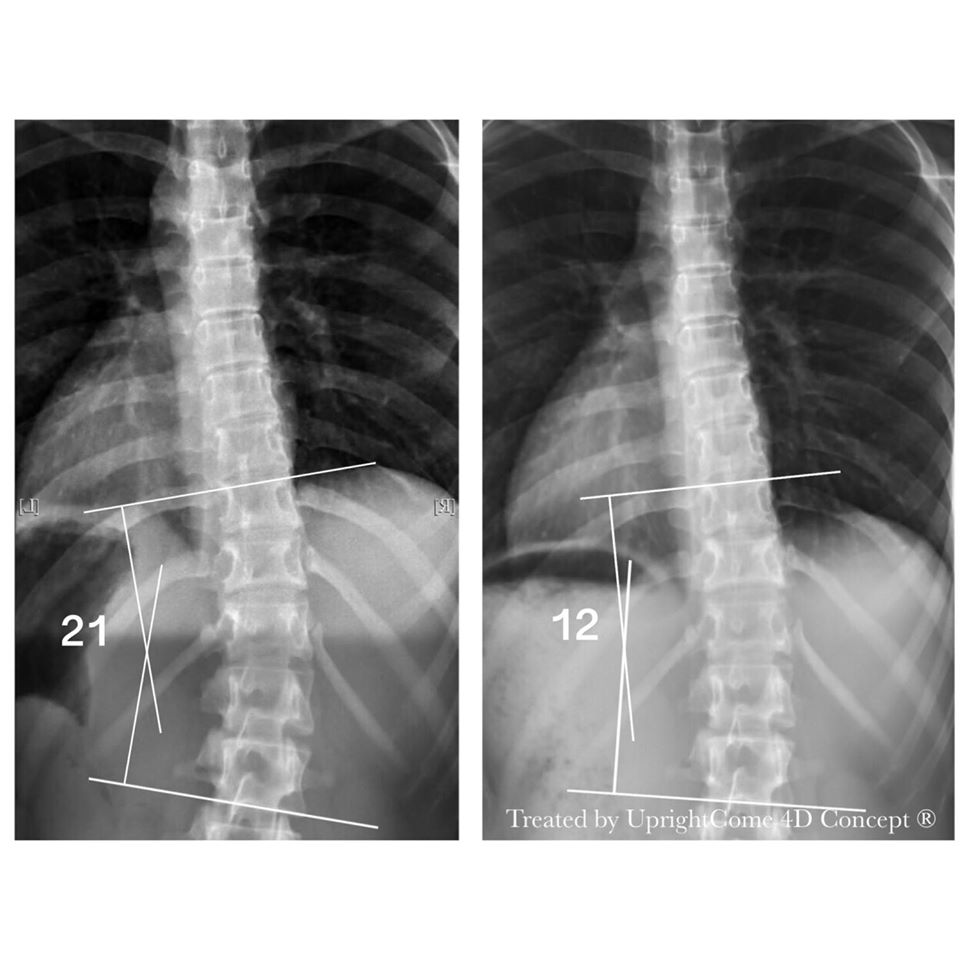

你的夢想是什麼?台北 16 歲側彎女孩答:我也想成為可以幫助別人的人。女孩正在持續追蹤治療中,小編被她的積極及認真打動,分享這份感動給大家。這是一位充滿正能量且勇敢的女孩,在課業壓力龐大的高中生活下,同時進行「 4D 側彎專屬治療療程」,沒有背架,憑藉著我們一起的努力,側彎度數與旋轉逐漸改善,也萌發成為「物理治療師」的夢想!